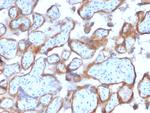

Cytokeratin 7 (Glandular and Transitional Epithelial Marker) Antibody in Immunohistochemistry (Paraffin) (IHC (P))

Cytokeratin 7 (Glandular and Transitional Epithelial Marker) Antibody (3855-MSM12-P0) in IHC (P)

Formalin-fixed, paraffin-embedded human Ovarian Carcinoma stained with Cytokeratin-7 Mouse Monoclonal Antibody (KRT7/2200). {{ $ctrl.currentElement.advancedVerification.fullName }} 验证信息 View more